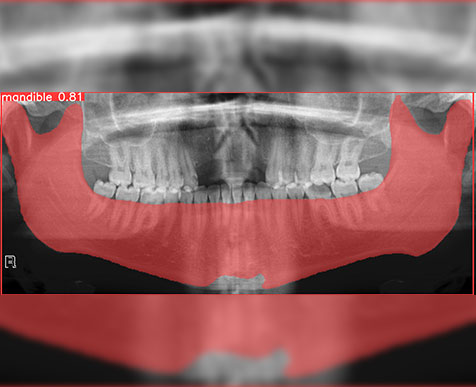

Arch Segmentation.